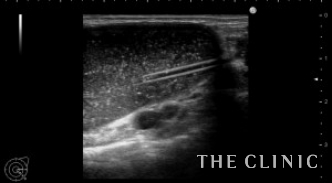

こちらは、多発するヒアルロン酸のしこり治療の症例です。

これまで2回他院でヒアルロン酸豊胸を行っていますが、たくさんのしこりができてしまい当院へ来られました。

両側の皮下、乳腺下、大胸筋内と30個以上のしこりを認めました。

一つ一つエコー下にヒアルロニダーゼを注入して吸引除去しました。

わずかに残存していますが、ほぼしこりは消失しました。

ヒアルロン酸注入によるしこりのエコー診断カルテ